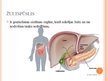

Žultspūšļa un žultsceļu ķirurģiskās slimības